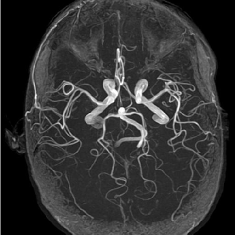

(a) Shepp-Logan phantom

Refer to caption

(b) FLAIT brain

(c) Lumbar spine

(d) Circle of Willis

Figure 2: Test Images.

We turn now to test TDIHT for high dimensional signals. We test the performance of several MRI images: the Shepp-Logan phantom, FLAIT brain image, T2 Sagittal view of the lumbar spine and the circle of Willis. The first image is of size 256×256256256256\times 256, while the other are of size 512×512512512512\times 512. They are all presented in Fig. 2.

We focus on the recovery of these images from a few number of Fourier measurements. With 𝛀𝛀{\mathbf{\Omega}} set to be the undecimated Haar transform with one level of resolution (redundancy four) and 𝐃𝐃\mathbf{D} its inverse transform, we succeed to recover the phantom image using only 181818 sampled radial lines, which is only 6.5%percent6.56.5\% of the measurements. This number is only slightly larger than the number needed for GAP, relaxed ASP (RASP) and Relaxed ACoSaMP (RACoSaMP) in [10, 38]. The advantage of TDIHT over these methods is its low complexity as it requires applying only 𝐌𝐌{\mathbf{M}} and its conjugate and 𝛀𝛀{\mathbf{\Omega}} and its inverse transform while in the other algorithms a high dimensional least squares minimization problem should be solved. Note also that for AIHT and RAHTP the number of radial lines needed for recovery is 353535 and for IHT (with the decimated Haar operator with one level of resolution) we need more than 505050 radial lines.